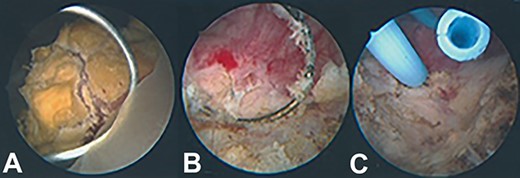

As bladder malignancy could not be ruled out, the patient was booked for simultaneous transurethral resection of bladder tumour (TURBT) + trans-perineal biopsy. Intraoperatively, digital rectal examination of the prostate revealed a firm left lobe. A 2–3 cm calcified mixed solid-papillary growth sitting in front but not involving the left ureteric orifice was seen and completely resected (Fig. 2A, B)—this was thought to be a bladder malignancy. Importantly, it was not in direct continuity with the prostate lobes so was in fact a distinct entity in itself. The bladder neck was very high with a prominent median lobe, so a limited TURP was performed to resect the base of the growth. Another nodule was seen and resected on the left inter-ureteric bar. The left ureteric orifice was preserved but, given it was very close to the resection site, a ureteric stent was inserted (Fig. 2C). Trans-perineal biopsies were obtained in the same sitting.

Intraoperative appearance of bladder lesion. (A) Prior to resection; (B) following resection; (C) following ureteric stent insertion.